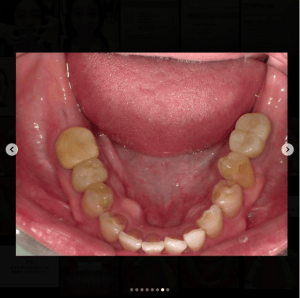

銀歯の中にできた虫歯の症例です。

「痛くないから今は虫歯がない」と話す方がいらっしゃいますが、それは大きな間違いです。

大人になってからの虫歯は痛みが出ることの方が圧倒的に少なく、口の中の病気は基本的に自覚症状と病気の重さが比例しません。

全ての銀歯の中に虫歯があるわけではありませんが、以下の理由から虫歯には注意が必要です。

1.銀歯はかけたり割れたりすることは絶対にないが、力がかかると”たわむ”

→ゆえに汚れが隙間に入りやすい

2.接着剤がつきやすいので、取れずらい

→ゆえに汚れもつきやすい

この症例のように、自覚症状が無くても銀歯を外してみたら大きな虫歯があるというケースも少なくありません。

しっかり検査、診断してくれるクリニックに定期的に行くことをおすすめいたします。